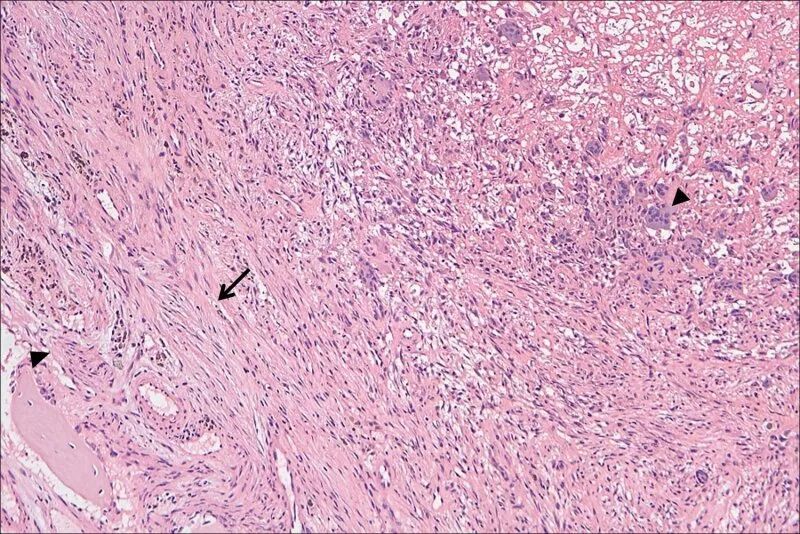

根据图1可见,除了髌骨粉碎性骨折之外,还可见右侧股骨中下段透亮度明显增加、骨小梁稀疏、骨皮质也显著变薄。追问病史,患者于1年前因右大腿疼痛检查发现右股骨骨囊肿形成并接受了内固定手术治疗(图1b可见内固定钢板)。患者出院之后病理报告才出来(图3),显示骨组织很少,绝大部分被纤维组织代替,同时可见大量多核巨细胞,病理科的同事立即意识到这不是一例简单的外伤引起的骨折,而是一种病理性骨折,高度怀疑甲旁亢引起的纤维囊性骨炎或骨巨细胞瘤。

图3.组织病理:少量骨组织(左下三角),大量纤维组织(中间箭头),巨细胞(右上三角)